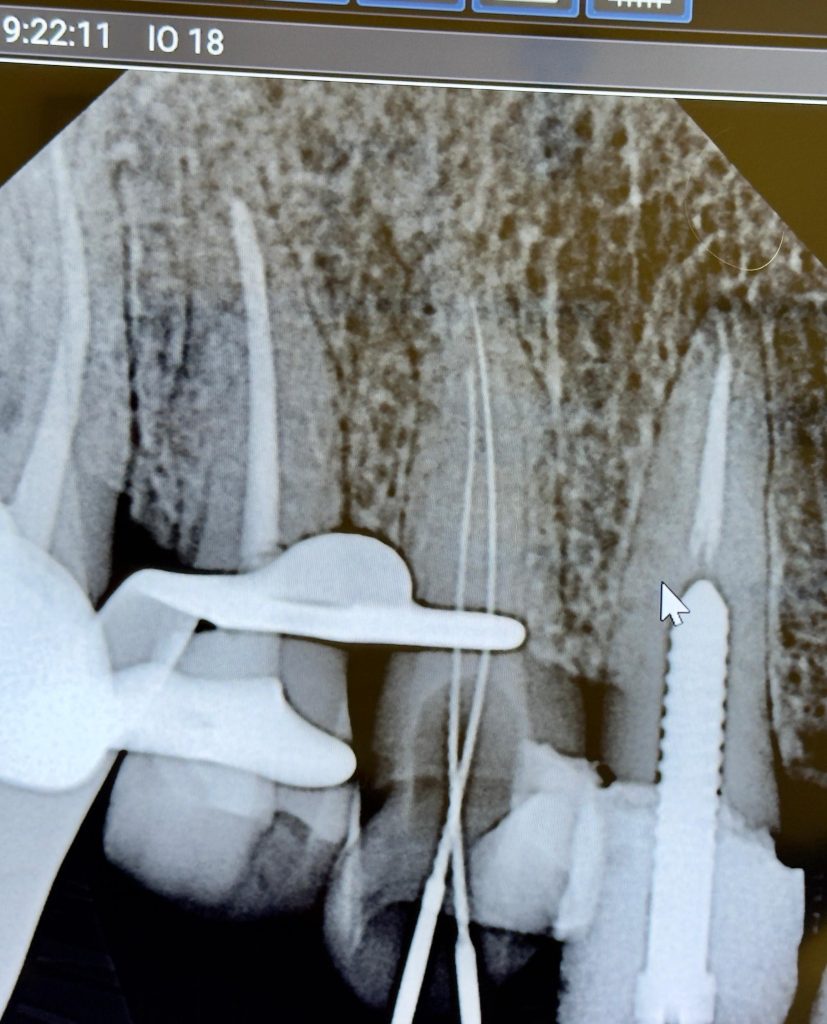

Radiographic Findings

- Previous endodontic treatment visible in UL3 and UL6

- Inadequate obturation and coronal leakage

- Widened PDL space on UL6

- Normal apical architecture on other teeth

- No sinus tract present

ENDODONTIC TREATMENT PROTOCOL

- Isolation: Achieved using full quadrant rubber dam isolation

- Canal preparation: Rotary NiTi system

- Irrigation: NaOCl + EDTA final rinse

- Obturation: Single-cone technique using resin-based Kerr sealer

- Coronal seal: SDR composite immediately post-obturation